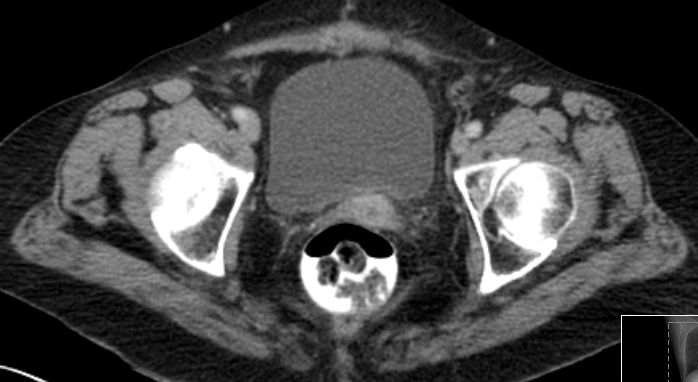

Scheidenvorderwand |

89jährige Frau mit einen ca. 3 cm großen gut tastbaren Rezidiv an der Scheidenvorderwand. Sonographisch Blasenwand infiltriert. Cystoskopie: Vorwölbung aber keine Infiltration der Mukosa.![]() |